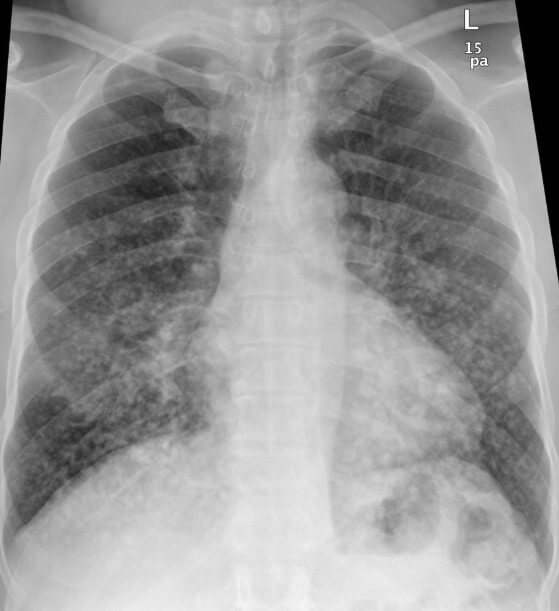

| Диагностика | Клиническая картина, лабораторные анализы (гипоксемия, анемия, тромбоцитопения, повышение уровня липазы), рентген грудной клетки (диффузные инфильтраты), КТ легких, МРТ головного мозга. | Нет специфического лабораторного теста. Диагноз ставится на основании совокупности клинических и инструментальных данных. |

Для подтверждения диагноза выполняется рентгенография органов грудной клетки, которая позволяет выявить засветы, указывающие на наличие жировых структур в сосудах малого круга.